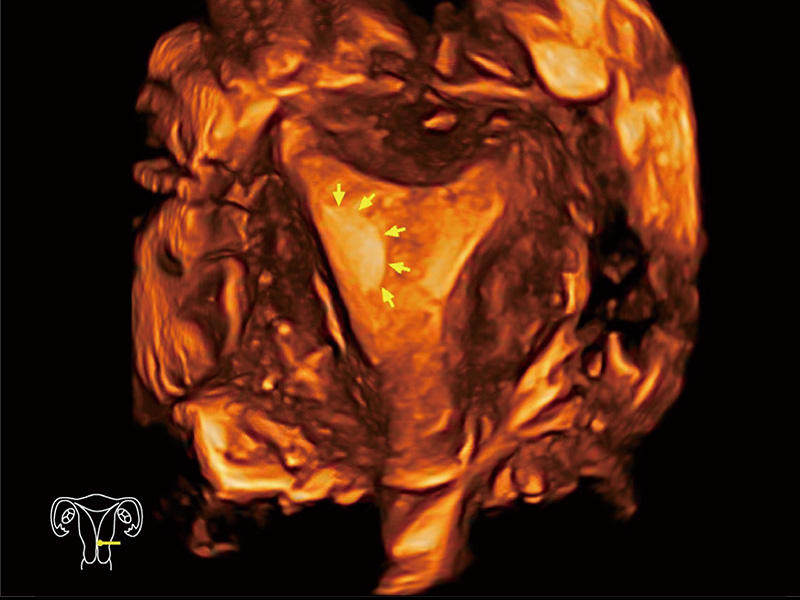

临床图

中央型宫腔粘连

超声引导下胚胎移植